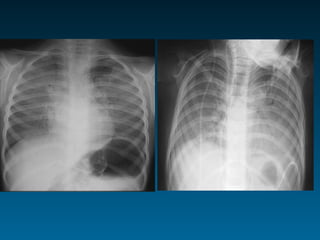

Θύμος στον παιδιατρικό θώρακα

Λέξεις κλειδιά: μαλακός ιστός (wavy), πρόσθιο μεσοθωράκιο

Θεωρείται πρόβλημα: σε ηλικία πάνω από 6 ετών

Θύμος=πρόσθιο μεσοθωράκιο

συνήθως ανώτερο

Θύμος

•     Διεύρυνση ανώτερου πρόσθιου

μεσοθωρακίου

•     Ευγενική τριγωνική δομή

•     Ακεραιότητα πνευμονικών δομών

•     Παιδιά έως 6 ετών

• Εναλλακτικά της α/ας ΥΧ       -ΥΤ-ΜΤ